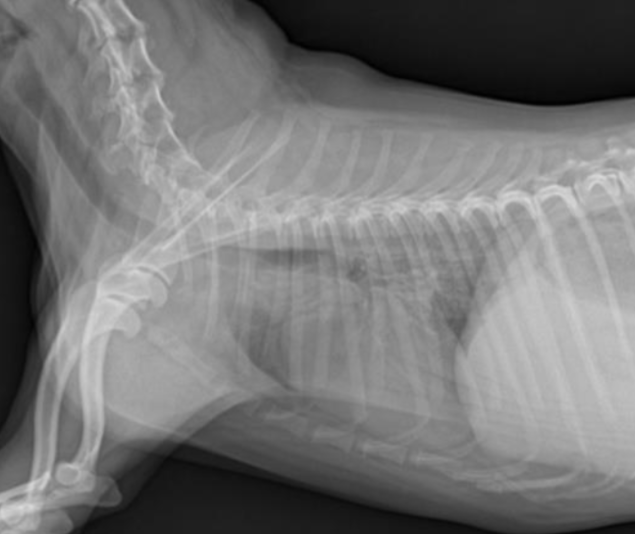

| RL (Right Lateral) | LL (Left Lateral) |

|---|---|

![]() | ![]() |

| 더 oval함. | 심장이 더 둥글게 보임(round). |

| 디테일한 심장 관찰에 좋음. | 폐혈관 촬영에 좋음. |